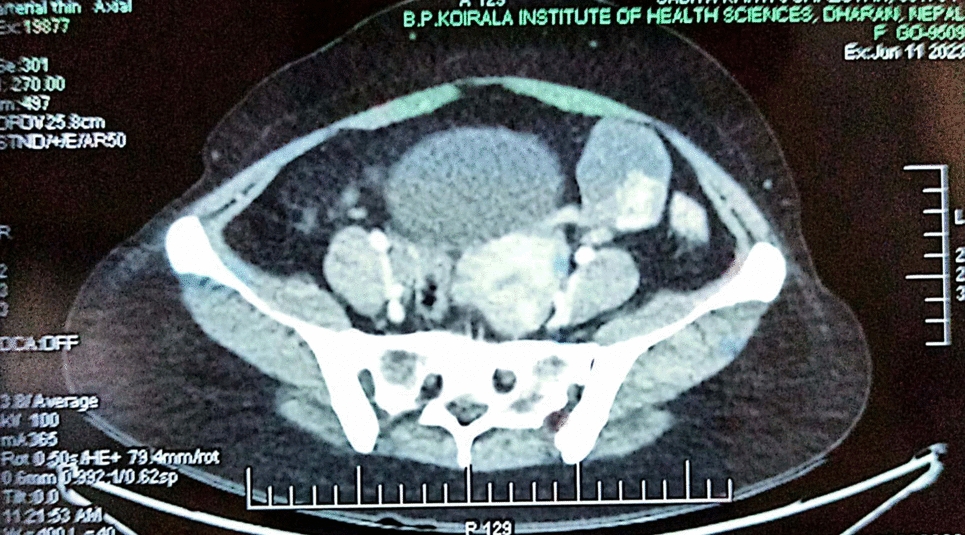

Three female patients with suspected ovarian tumors, based on clinical symptoms, imaging, and elevated CA-125 levels, were reviewed. Each patient underwent staging laparotomy, followed by histopathological examination of the resected masses. Surgical findings, including the presence of sulfur granules and Splendore-Hoeppli phenomenon, confirmed actinomycotic infection in all cases. Post-surgical treatment included prolonged antibiotic regimens tailored to each case.

Histopathology revealed that all patients had extensive actinomycotic infection, marked by inflammatory and fibrotic changes. Notably, none of the patients had a history of IUD use, which is atypical for pelvic actinomycosis cases. Following surgery and antibiotic treatment, all patients achieved full recovery without recurrence, underscoring the effectiveness of this combined approach.